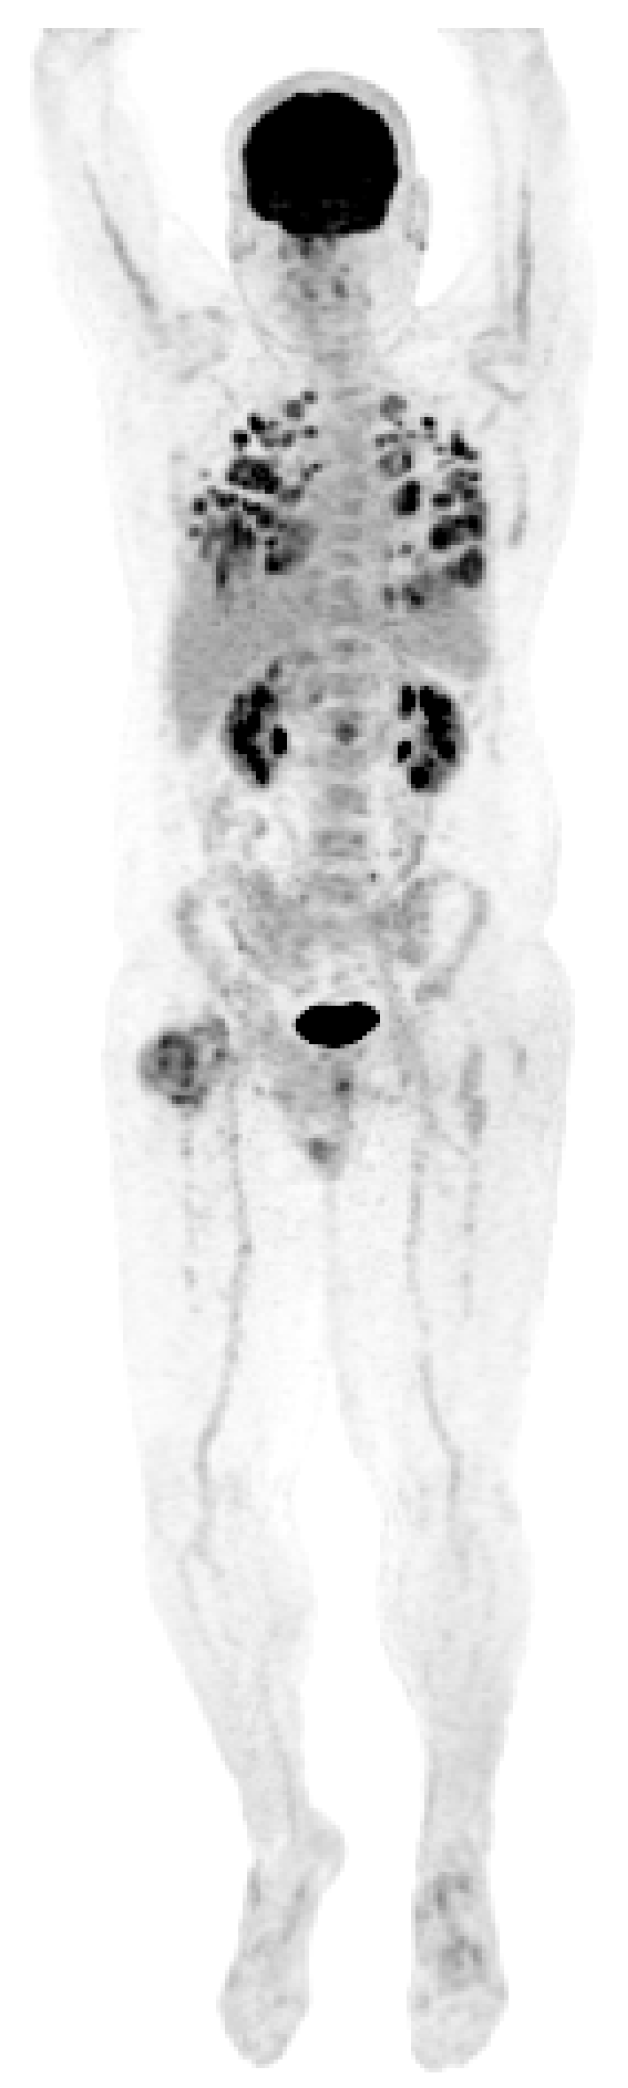

A new hypermetabolic lesion in the right intertrochanteric region was observed on PET/CT two months following the second wedge resection. A CT-guided biopsy of the lesion was consistent with metastatic GCT. The patient developed widely disseminated recurrent disease (Figure 5) and he ultimately expired one month later at 190 months following his initial diagnosis.

Figure 5.

PET scan showing diffuse lung metastases and a right proximal femoral metastasis.